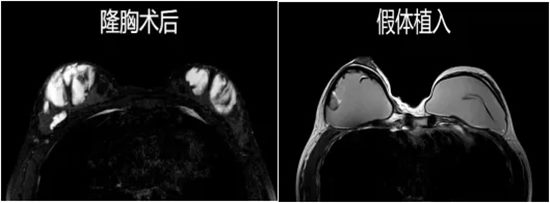

进行过隆胸手术的女性,能够检查假体是否破裂,让美丽与健康并存。